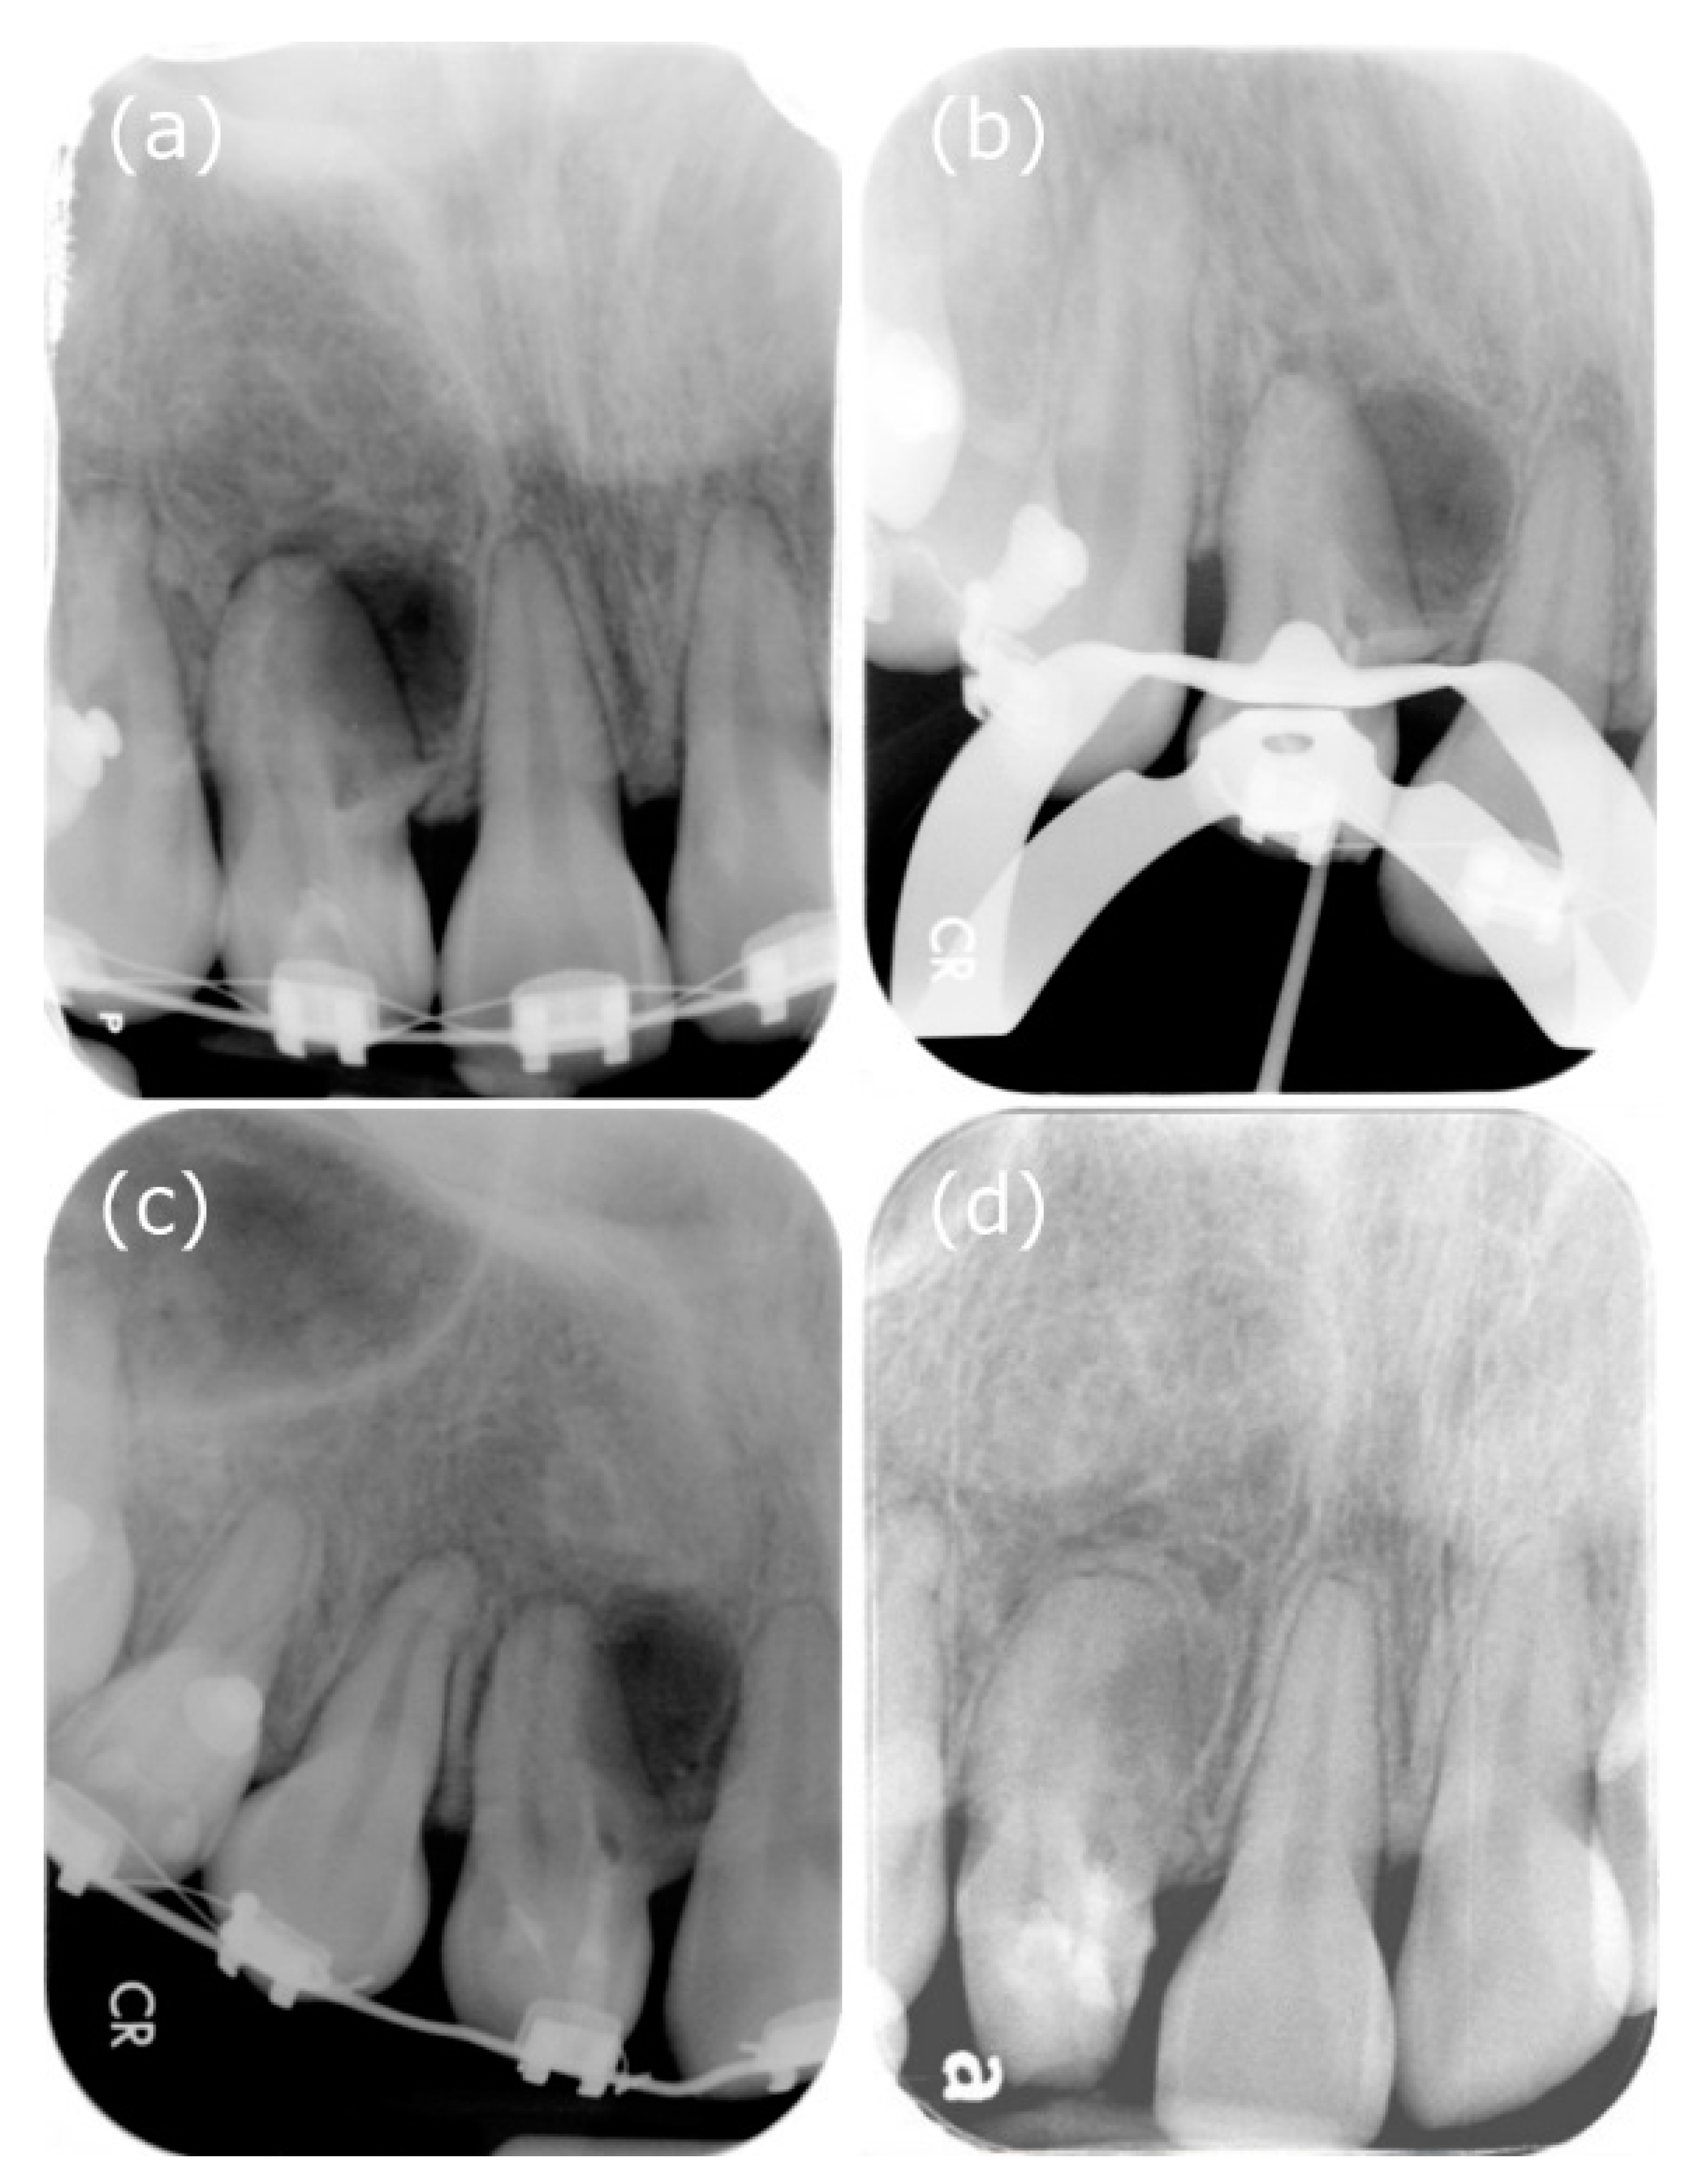

We can observe the radiolucent invagination from the periapical film (Figure 2a), which looks like a tooth is inside another. A radiopaque invagination of the dentin lined by the enamel could be observed in the crown. A “pseudo-canal” was located near the mesial side and extended from the enamel invagination to approximately the cemento-enamel junction, spreading and forming the opening of the pseudo canal, with a lesion at the mesial and lateral part of the root. Considering the irregular shape, root resorption in the “pseudo-canal” was suspected.

Figure 2.

Periapical films during the treatment procedure. (a) X-ray showed that the radiolucent invagination looks like a tooth inside another. Additionally, there was dentin invagination lined by enamel into the main canal space, spreading into the mesial part of the middle root. Tooth 12 appeared to be associated with a large peri-invagination radiolucent lesion around the opening of the invagination near CDJ. (b) Measurement of the working length. (c) Mineral trioxide aggregate was used to seal the invagination. (d) Follow-up at two postoperative years. The patient complained of no clinical symptoms, and the peri-invagination lesion had healed significantly.